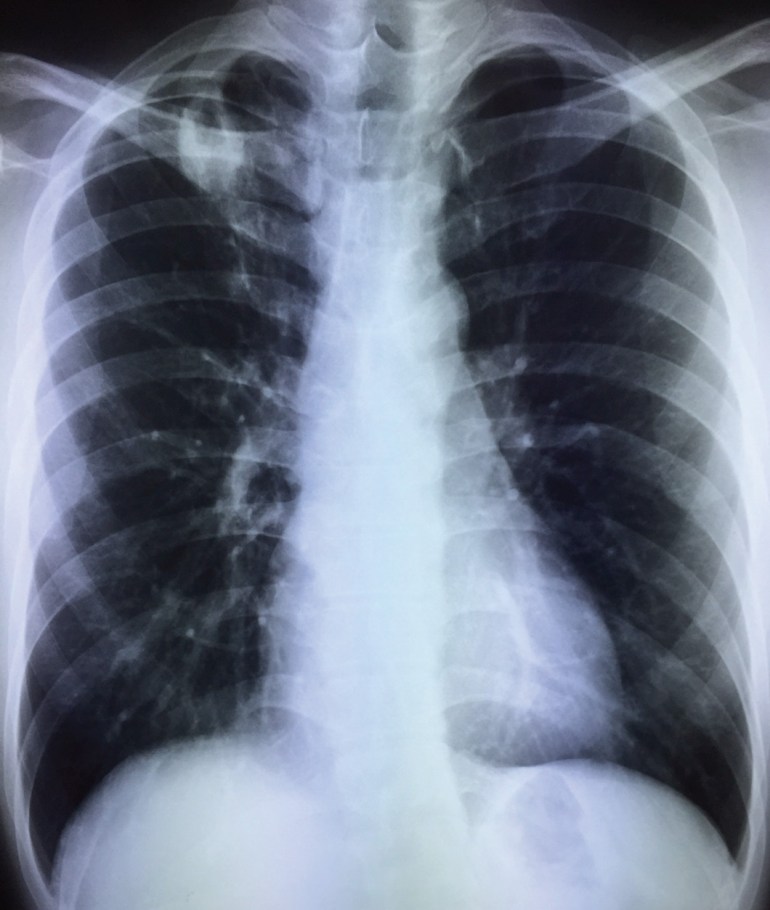

A young local man in his late 20’s, previously well, was found on pre-employment screening to have abnormal chest X-ray. He was otherwise asymptomatic.

He had started to develop a dry cough a week later, although he did not have any fever or other constitutional symptoms. A repeat chest X-ray showed progression of radiological changes.